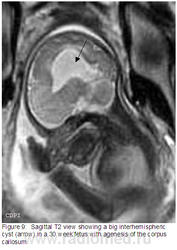

1. На аксиальной Т2 колпоцефалия (стрелки) у 29 недельного плода.

9. На саг.Т2 большая межполушарная киста (стрелка) у 30 недельного плода с агенезией мозолистого тела.